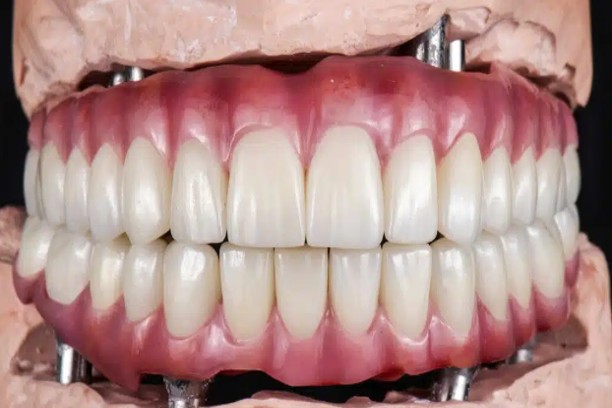

All-on-4 Implants

Full-arch restoration using just 4 implants, often completed in a few days.

All-on-6 / All-on-8 Implants

Strong support for full-mouth reconstruction, ideal for multiple missing teeth.